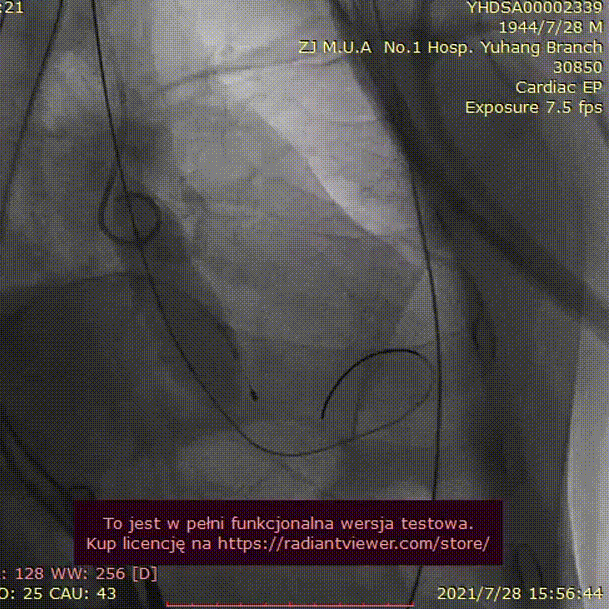

手术过程:

23mm球囊预扩

(有腰征,无返流)

开始释放后再次定位

23mm球囊后扩

植入后造影

术后压差1mmHg

术中经食道心超评估:

人工主动脉瓣:植入深度 7mm,峰值流速1.2m/s,峰值压差6mmHg,平均跨瓣压差3mmHg,原左-右冠窦结合部微量瓣周漏。